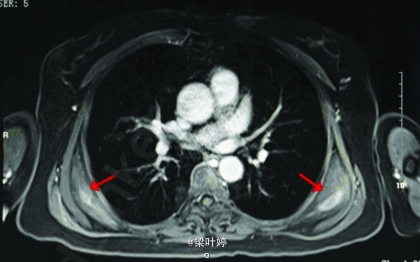

查体:双侧肩胛下角区域可扪及一直径约5cm 硬质类圆形包块,固定。余无特殊。 CT提示:双侧背阔肌及前锯肌深面对称性病变,增强后不均匀强化,周围脂肪间隙清楚。 MRI示::双侧对称性病变,位于背阔肌及前锯肌深面,增强后斑片状强化,周围脂肪间隙清晰,局部与肋骨骨膜关系紧密。